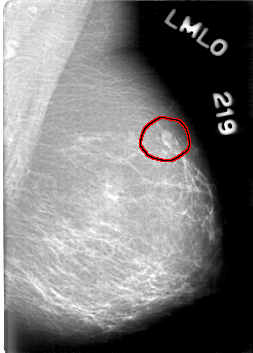

D_4076_1.LEFT_MLO

LEFT_MLO LINES 5281 PIXELS_PER_LINE 3781 BITS_PER_PIXEL 12 RESOLUTION 43.5 OVERLAY

FILE: D_4076_1.LEFT_MLO.OVERLAY

TOTAL_ABNORMALITIES 1

ABNORMALITY 1

LESION_TYPE MASS SHAPE LOBULATED MARGINS OBSCURED

ASSESSMENT 0

SUBTLETY 4

PATHOLOGY BENIGN

TOTAL_OUTLINES 1

BOUNDARY